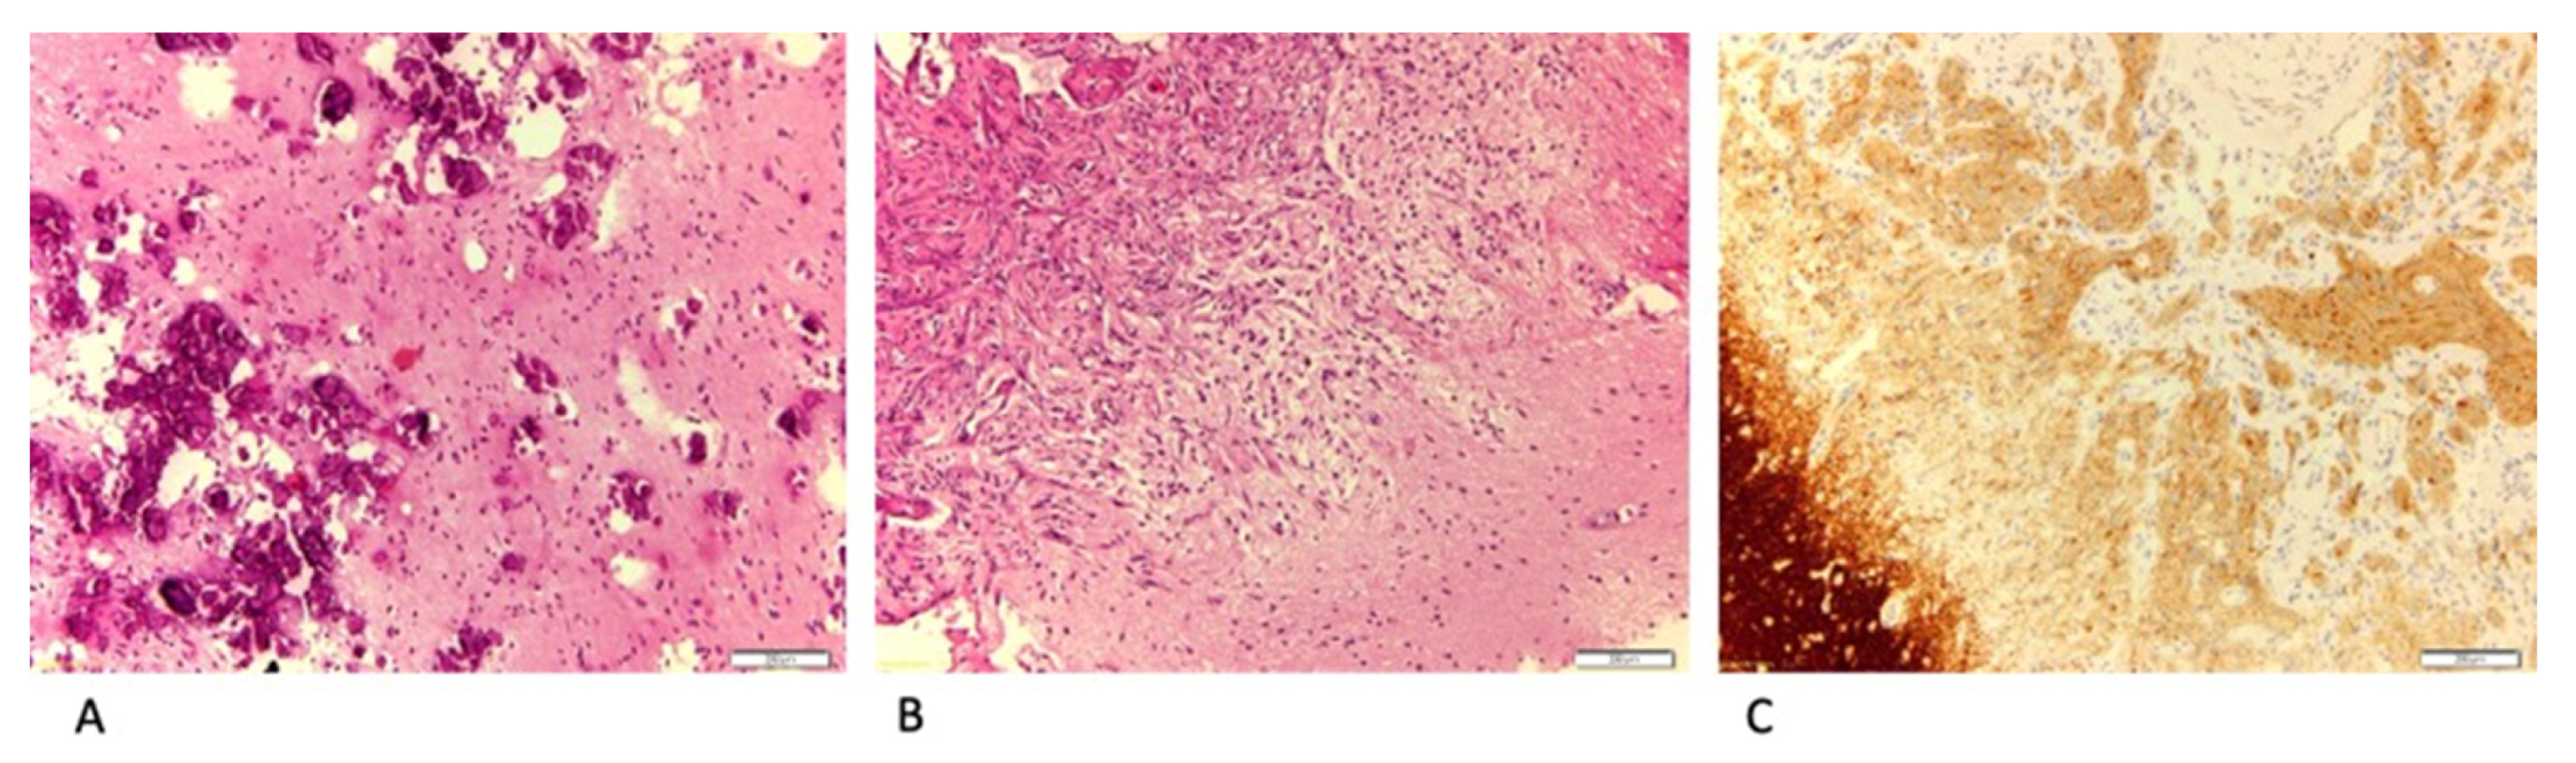

3.1. LEATs with MI (Group 1)